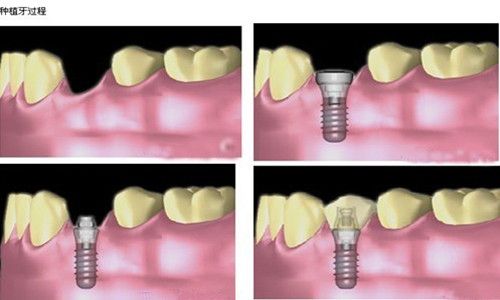

镇江现代口腔午休牙齿种植方案,上班族两小时重获自信

在镇江这座充满活力的城市里,上班族们每天奔波于工作与生活之间,时间成为较奢侈的资源。牙齿缺失不仅影响咀嚼功能和面部美观,...

重庆美连口腔当天种牙当天用真实可行吗?即刻种植技术

重庆美连口腔当天种牙当天用真实可行吗?重庆美连口腔的当天种牙当天用服务经临床验证真实可行,但需满足严格适应症:骨量充足、...